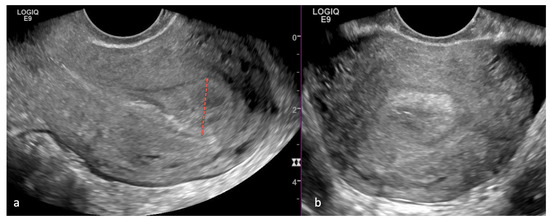

5.1. Ultrasound (US)

- Ziogas, A.; Xydias, E.; Kalantzi, S.; Papageorgouli, D.; Liasidi, P.N.; Lamari, I.; Daponte, A. The diagnostic accuracy of 3D ultrasound compared to 2D ultrasound and MRI in the assessment of deep myometrial invasion in endometrial cancer patients: A systematic review. Taiwan. J. Obstet. Gynecol. 2022, 61, 746–754. [Google Scholar] [CrossRef] [PubMed]

- Spagnol, G.; Noventa, M.; Bonaldo, G.; Marchetti, M.; Vitagliano, A.; Laganà, A.S.; Cavallin, F.; Scioscia, M.; Saccardi, C.; Tozzi, R. Three-dimensional transvaginal ultrasound vs magnetic resonance imaging for preoperative staging of deep myometrial and cervical invasion in patients with endometrial cancer: Systematic review and meta-analysis. Ultrasound Obstet. Gynecol. 2022, 60, 604–611. [Google Scholar] [CrossRef] [PubMed]

- Green, R.W.; Epstein, E. Dynamic contrast-enhanced ultrasound improves diagnostic performance in endometrial cancer staging. Ultrasound Obstet. Gynecol. 2020, 56, 96–105. [Google Scholar] [CrossRef] [PubMed]